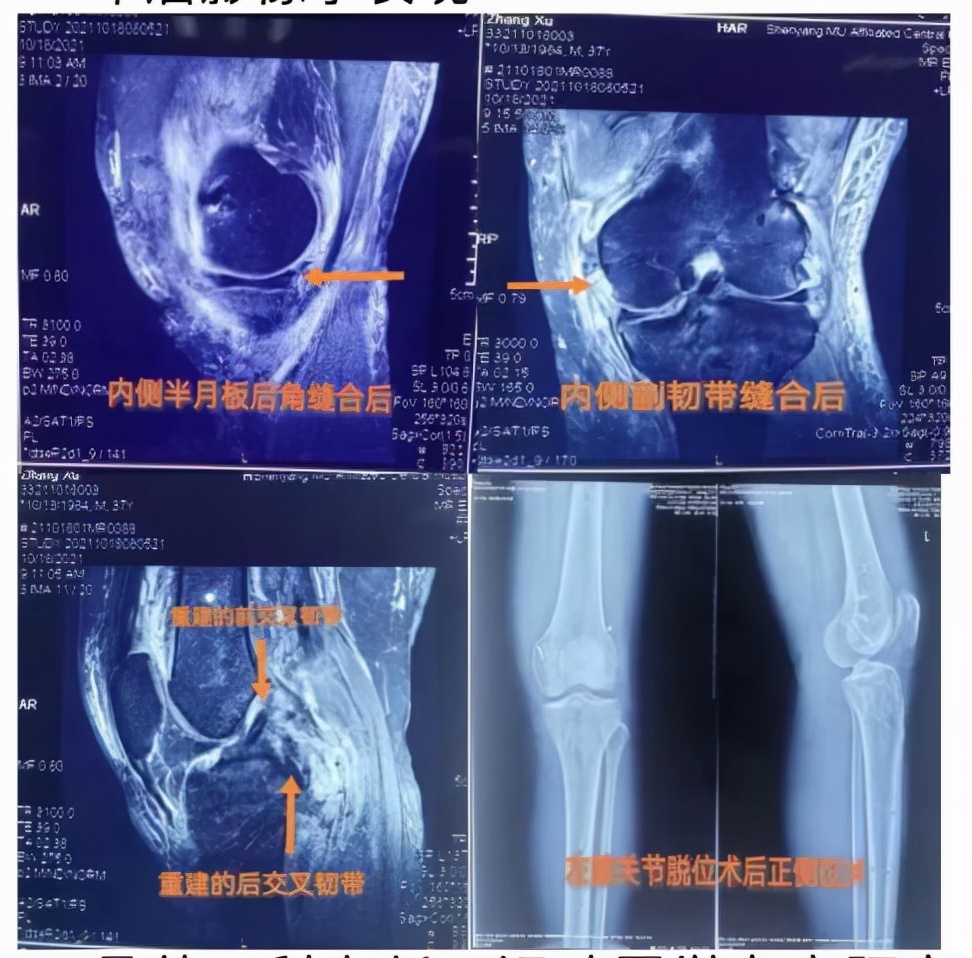

入院后,骨外二科主任、运动医学专家阿良高度重视小张的情况,经过科室团队认真反复讨论,确定了最佳手术治疗方案,急诊给予左膝关节脱位手法复位术,决定二期取自体双侧腘绳肌肌腱对其实施膝关节镜下前后交叉韧带重建术,内侧副韧带修补术,内侧半月板后角撕裂缝合术。手术如期进行,整个团队配合默契,精准操作,完成一个又一个部位的重建,经过近3个小时的持续奋战,手术顺利结束,一次性解决所有损伤,效果非常满意。目前,小张病情平稳,恢复良好,正在逐步加强膝关节功能锻炼,这让他重新燃起了生活的希望,小张及家属非常感激。

术后影像学表现